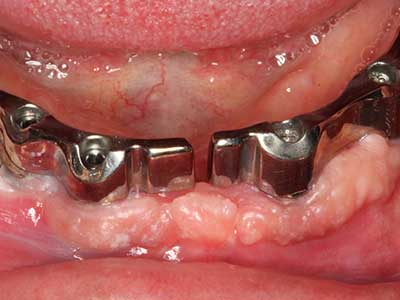

Fig. 15: la radiografia dopo un follow up di un anno mostra condizioni stabili a livello osseo.

Fig. 16: anche le condizioni intra-orali sono stabili, con l'incorporazione degli impianti nella gengiva cheratinizzata.